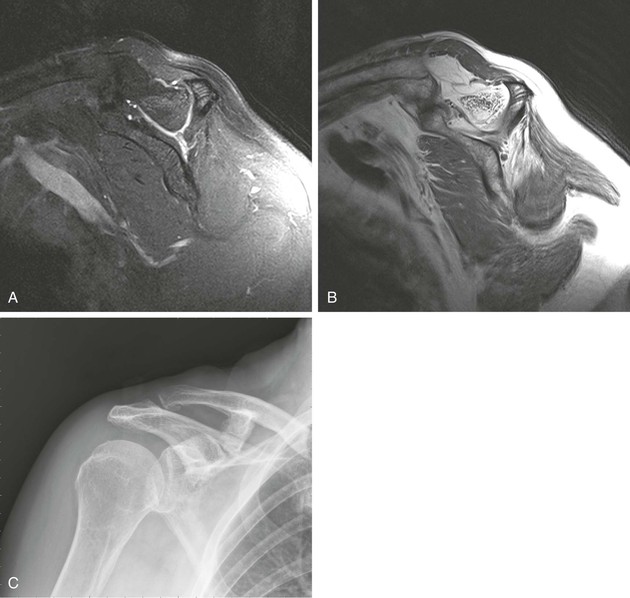

Glenohumeral instability is a complex topic in terms of diagnosis and treatment of shoulder injuries. The anatomic configuration of the shoulder allows extensive range of motion, but it also predisposes the shoulder to instability. Instability can be the result of insult to any of the static or dynamic stabilizers of the joint. The clinical definition of shoulder instability is the symptomatic displacement of the humeral head out of the glenoid fossa, and various schemes have been developed to classify shoulder instability. These schemes include the temporal relationship of the instability to previous trauma (first time vs. recurrent), the degree of instability (subluxation vs. dislocation), and the direction of instability (anterior inferior, posterior, inferior, anterior superior, posterior superior, or multidirectional). Instability can also be related to congenital factors including glenoid dysplasia. For more details on the diagnosis and classification of instability, see Chapters 46, 47, and 48.

Although the initial imaging study after suspected shoulder dislocation or recurrent glenohumeral instability is usually conventional radiography, it provides only a limited evaluation of the shoulder, with detection of such abnormalities as fractures, persistent dislocation, and abnormal soft tissue calcifications. MRA is considered the most accurate way to study the labrum and capsule structures. As described earlier, MDCT arthrography has been reported to be comparable to MRA for evaluating the labrum and capsule.8,25

Conventional radiography is often complementary to more sophisticated imaging techniques in the evaluation of glenohumeral instability. The imaging protocol for conventional radiography varies, depending on personal preference, but it should include the basic views, which will enhance the detection of osseous abnormalities. For patients with a history of antecedent trauma, views should be selected that optimize visualization of the Hill-Sachs deformity, anterior trough defect, and Bankart lesion.136 The Garth view,137 the AP view with the shoulder in internal rotation, the axillary view, and the Stryker notch view improve detection of the posterior Hill-Sachs deformity and of the anterior trough defect (see Fig. 44-35). The anterior and posterior glenoid rim is best imaged on the axillary view or one of its many variations. An osseous Bankart lesion involving the anteroinferior glenoid rim is best visualized on the Garth view or the West Point view.3 The patient's condition should also be taken into consideration in selecting radiographic views because the standard axillary view may be difficult to obtain in the setting of acute trauma. In these situations, one of the many axillary variants may be easier to obtain. In the setting of recurrent subluxation with no antecedent trauma, it is recommended that two tangential views be obtained to identify subtle subluxation of the humeral head. A true anteroposterior glenohumeral (Grashey) view will aid in the detection of inferior subluxation, and one of the axillary view variants will demonstrate anterior or posterior subluxation.

The radiographic findings associated with glenohumeral instability include the Hill-Sachs and Bankart osseous abnormalities, which occur when the posterior aspect of the humeral head has an impact on the anteroinferior glenoid rim at the time of anterior dislocation. The Hill-Sachs lesion is seen as flattening or a wedge-shaped defect involving the posterosuperior aspect of the humeral head; the bony Bankart lesion is seen as a small fracture or area of cortical irregularity involving the anteroinferior glenoid rim. Although these radiographic findings lack sensitivity, they are specific for previous anterior dislocation and indicate that injury has occurred to the labroligamentous complex, which may predispose the patient to recurrent glenohumeral instability. At the time of posterior dislocation, the anterior aspect of the humeral head has an impact on the posterior glenoid rim, creating an anterior trough defect in the anterior aspect of the humeral head and a “reverse Bankart” lesion involving the posterior glenoid rim. Subluxation can be a subtle radiographic finding that may indicate glenohumeral instability, and it is best detected on tangential views of the glenohumeral joint. The center of the humeral head should be centered within the glenoid fossa, and any asymmetry may indicate subluxation or persistent dislocation (Box 44-5).

MRI and MRA are the main imaging modalities used in the evaluation of a patient with glenohumeral instability.22,23 Even with 3-tesla magnets, MRA demonstrated superior sensitivity compared with routine MRI in a study of 150 consecutive examinations for detecting SLAP lesions and labral tears.138 Joint distention with fluid outlines and separates the normal anatomic structures, allowing more accurate depiction of subtle lesions (Fig. 44-36). CT imaging with sagittal and coronal reconstructions remains the study of choice for detecting and depicting the size and location of a fracture fragment of the anteroinferior glenoid rim (see Fig. 44-4), which can be useful in presurgical planning in patients with large osseous Bankart lesions. As previously stated, MDCT arthrography is accurate for detecting instability lesions and very useful for patients who cannot undergo MRA or lack access to MRI services. The addition of MRI stress views, such as the ABER view (see Fig. 44-37, C), may improve visualization of a nondisplaced tear in the anterior inferior labrum.54